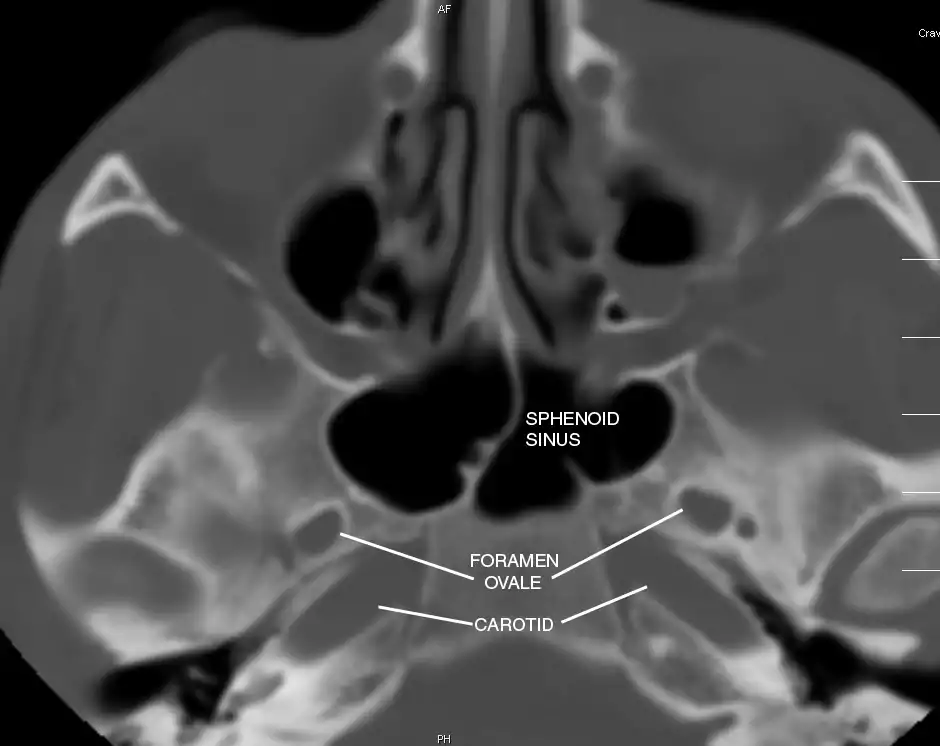

Sphenoid Sinus has 12 close structures: II, III, IV, V1, V2, VI, Vidian Nerve, Carotid artery, Brain, Dura, Pituitary.

V2 = Maxillary division, Trigeminal Nerve: exits foramen rotundum, superomedial to V3's foramen ovale.

C = Carotid Artery: often with bony dehiscence into sphenoid. Together with CN II forms opticocarotid recess.